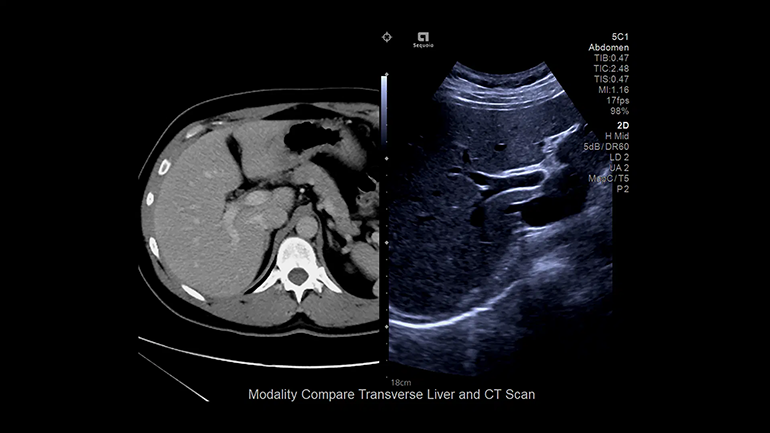

Технология суммации изображений

Эта технология в реальном режиме времени позволяет суммировать УЗ-изображения с диагностическими изображениями, полученные при использовании других диагностических методов визуализации (КТ, МРТ к примеру) для повышения надежности визуализации при сложных интервенционных процедурах.

Технология Fusion Эта технология позволяет суммировать изображения, полученные при работе с разными диагностическими модальностями для повышения надежности визуализации при сложных интервенционных процедурах.